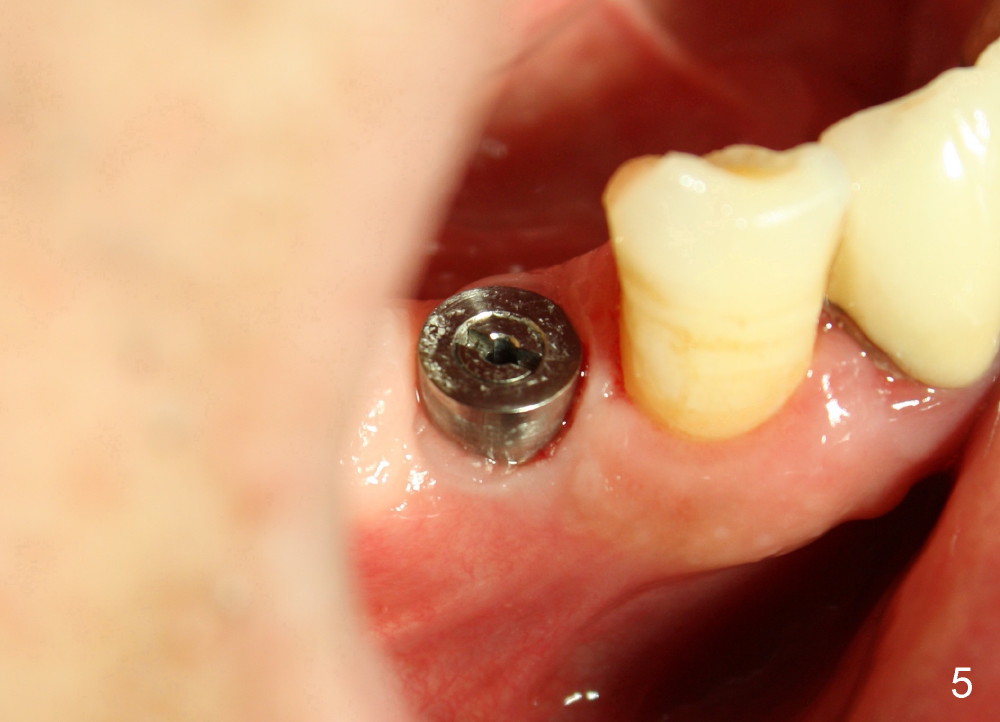

A 66-year-old man has poor dentition (Fig.1). Several teeth (x) including #28 need extraction and implants. The tooth #28 is extracted (Fig.2), followed by immediate implant (5x17 mm, Fig.3 I). There is more buccal gingival recession over the implant (Fig.4), which is less prominent 1.5 months postop (Fig.5). The definitive restoration is delivered less than 2 months postop (Fig.6), because of travel abroad. The patient agrees not to chew with the Emax crown. Five months later, he returns with chipped porcelain (Fig.7 arrowhead). It appears that immediate implant can survive early and over loading. More implants are necessary to share the masticatory loading. Since there is malocclusion, where to place implants appears to be critical (Model 3 30 4 5 6 7). There is no bone loss 4.5 years (Fig.8) or 5 years 8 months (Fig.9) post cementation.